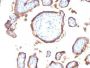

Applications IHC

IHC, FFPE (verified)

A431 cells. Placenta, Breast, Colon or Bladder cancer

IHC (FFPE) (verified)

Immunohistology formalin-fixed 2-4 ug/mL|Digest formalin-fixed tissues with Protease Sigma Cat. #P-6911 at 1 mg/mL PBS, pH 7.4 for 10 min at 37C|Flow Cytometry 0.5-1 ug/million cells/0.1 mL|Immunofluorescence 1-2 ug/mL|Optimal dilution for a specific application should be determined by user